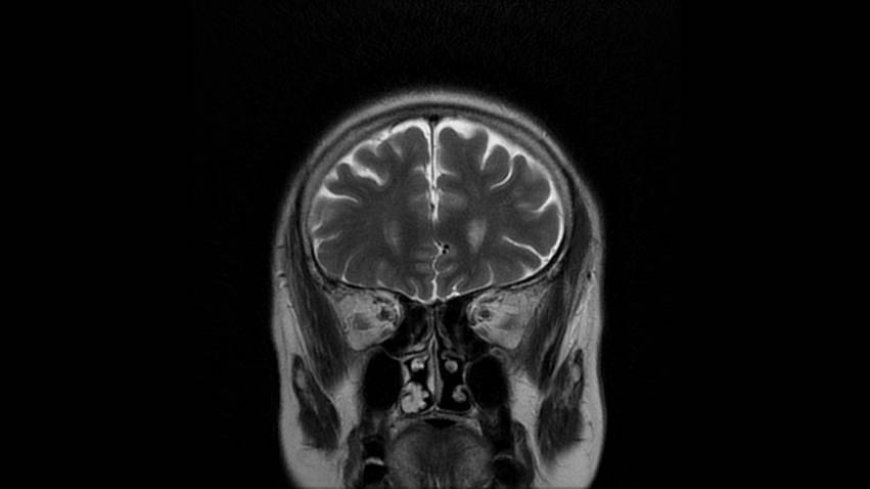

MRI of Brain

Coronal T2